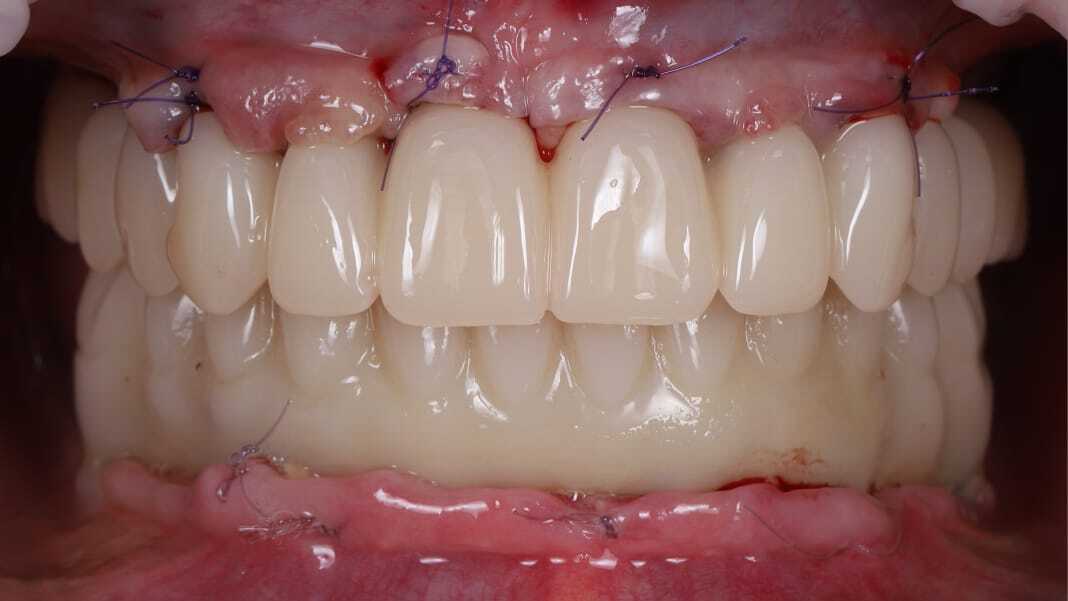

Константин Олегович Юшков

Планирование от результата. Выбор количества опор и материала постоянной конструкции. Работа с мягкими тканями на этапе провизорных.

До

После

Цифровые протоколы немедленной нагрузки с умеренной степенью атрофии